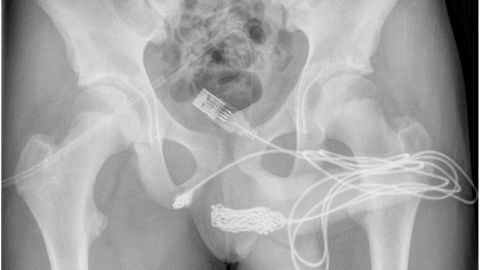

Un adolescente de 15 años ha sido intervenido de urgencia en Reino Unido después de introducirse un cabe USB por el pene según explica la revista médica Urology Case Reports en un informe con impactantes imágenes.

Un adolescente de 15 años anónimo de Londres, Reino Unido, se sintió impulsado por su curiosidad sexual y decidió hacer un experimento de insertar el cable USB en su pene para medir su longitud. Sin embargo, fracasó cuando el cable se atascó en su escroto.

Intentó quitárselo él mismo, pero el cable USB se enredó aún más y los dos extremos quedaron colgando de su pene. Al final el joven tuvo que acudir a urgencias y terminó sometiéndose a una cirugía de emergencia para retirar el cable USB. Su caso fue detallado en el artículo, titulado "Autoinserción uretral de un cable USB como experimentación sexual: informe de un caso", que se publicó en la revista médica Urology Case Reports junto con las impactantes imágenes.

Los padres del adolescente se vieron obligados a llevarlo a la sala de emergencias después de que orinó sangre debido al cable USB atascado en su pene. El personal del hospital no pudo retirarlo al principio, por lo que transfirieron al niño al University College Hospital de Londres para que recibiera la cirugia necesaria.

Los médicos tuvieron que cortar el músculo bulboesponjoso, el área entre los genitales y el ano, para sacar el cable USB. Pero no pudieron pasar la parte anudada del cable a través de ese corte antes de sacar las piezas restantes del cable eléctrico. Afortunadamente, el niño no necesitó más tratamiento y fue dado de alta al día siguiente.